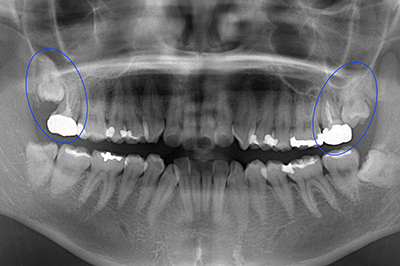

1.お口の中の診察しレントゲンやCT検査を行います。 検査により親知らずが神経に接している場合は、抜歯によって神経損傷のリスクがあるため、大学病院に紹介するか、2回抜歯法にて安全に抜歯をおこないます。

CT検査にて親知らずと神経が接してしる

右下の奥歯が重度の虫歯で抜歯と診断。親知らずの移植を計画。

抜歯と同時に親知らずを移植

骨の再生が認められる

経過は良好

治療期間 6ヶ月

費用 15万円(歯の移植)

第二大臼歯のな根が折れており抜歯と診断

第一大臼歯がすでに欠損しているのでこのままだと奥歯が2本失ってしまう為、第二大臼歯に親知らずを移植し、第一大臼歯部はインプラント治療を計画した。

治療期間 1年

費用 60万円(インプラント45万 / 歯の移植15万)